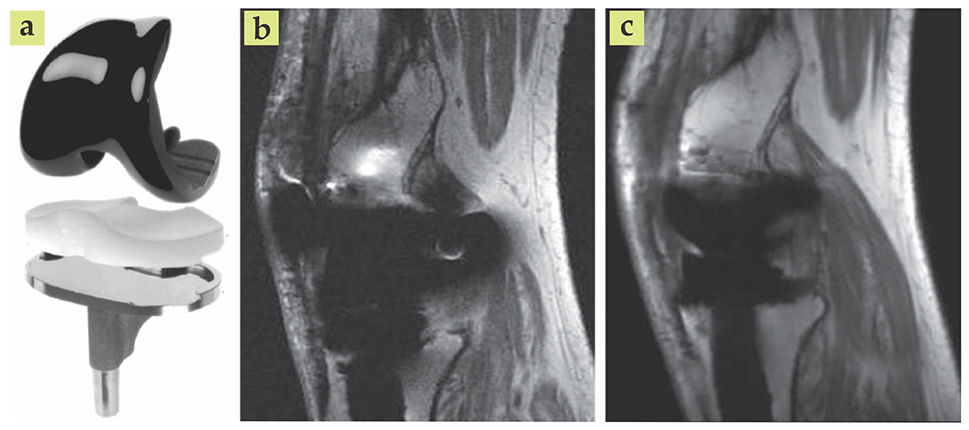

Alternatively, MRI provides the contrast needed to identify infection and some bone loss surrounding implants. The contrast arises due to the response of hydrogen atom spins in a uniform magnetic field: The spins precess at different rates depending on their chemical environment and the strength of the local magnetic field. (See the article by Felix Wehrli, Physics Today, June 1992, page 34 .) However, because bone and metal have vastly different magnetic susceptibilities, their interfaces give rise to sharp gradients that can distort the local magnetic field and thereby distort the acquired image, as shown in figure 4. Improvements in imaging and postprocessing techniques during past decades have helped eliminate those distortions. 15

PTO.v68.i4.40_1.f4.jpg

Figure 4. Metal-based implants, such as an artificial knee (a), often appear distorted in magnetic resonance images. The sharp difference between the magnetic susceptibilities of bone and metal creates magnetic field gradients that result in unfaithful images (b). Advanced imaging techniques and postprocessing algorithms can yield vastly improved results (c). (Adapted from ref. 15.)